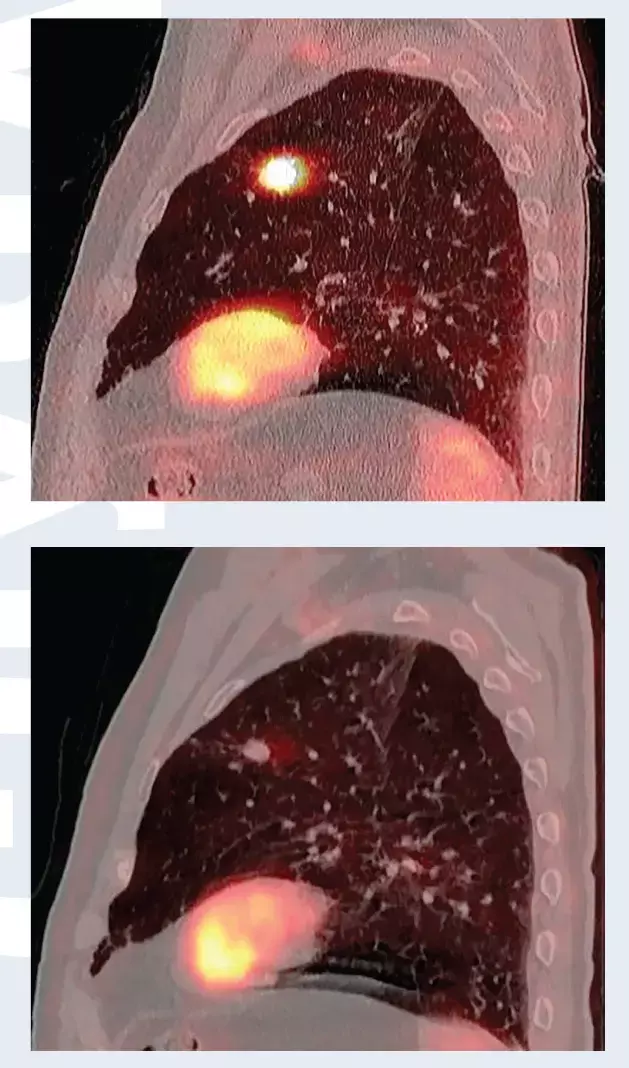

Установлен диагноз периферического рака верхней доли левого легкого cT1bN0M0, Ia стадия. В связи с выраженной сопутствующей кардиологической патологией и высоким риском осложнений хирургическое лечение не проводилось. Пациенту проведено три сеанса СЛТ с разовой дозой 18 Грей за сеанс, с интервалом через 1 день (рис. 1). По данным ПЭТ/КТ через 4 месяца после лучевой терапии опухоль уменьшилась в размерах, перестала накапливать фтордезоксиглюкозу (рис. 2). Имеет место полный метаболический ответ опухоли на лечение.

Рис. 2. ПЭТ/КТ до стереотаксической лучевой терапии (вверху) и 4 месяца спустя (внизу). Полный метаболический ответ опухоли на лечение.